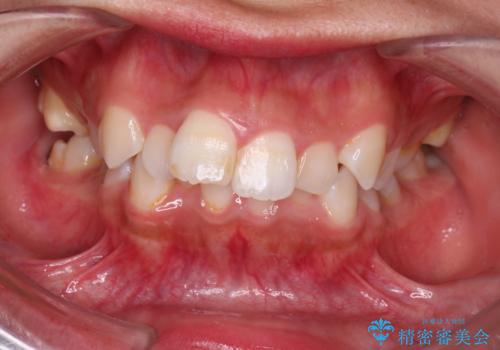

ディープバイト改善のためのインビザライン治療

- 治療計画

ディープバイトの治療には、奥歯の高さや前歯の位置に対する繊細な調整が必要です。本症例では、インビザラインによる歯列拡大を行うことで、噛み合わせを改善し、歯並び全体を整えました。治療過程では、歯間のスペースを確保するため、IPR(インタープロキシマルリダクション)を適宜行い、無理なく歯列の調整を行いました。治療後は、歯並びが大きく改善され、患者様の見た目にも大きな変化が現れました。インビザラインは透明で目立たず、治療中の見た目を気にされる患者様にも配慮した治療法です。